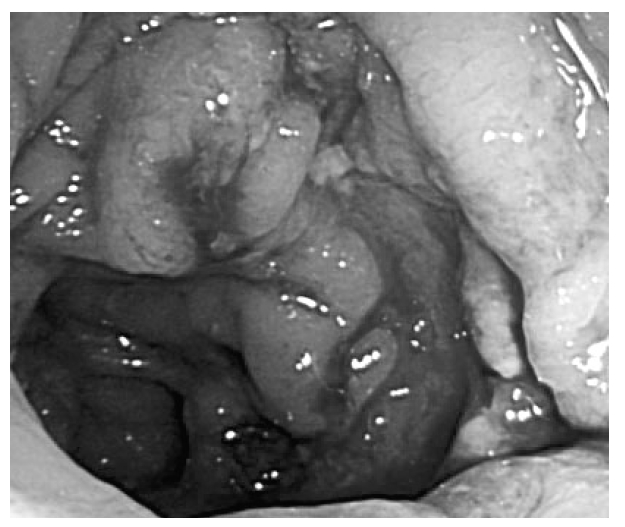

She was treated with prednisolone 50 mg/day (1 mg/kg/day) for control of arthralgia which caused the limited motion of both knee joints. Arthralgia was improved immediately but purpura spread to the upper trunk and face and improved slowly one month later. After six weeks, prednisolone was tapered to 20 mg/day. On the seventh week of hospitalization, she experienced abdominal pain and hematochezia and the hemoglobin was decreased to 7.0 g/dL. Gastrofibroscopic examination revealed hemorrhagic gastritis and colonoscopy revealed multiple ulcerations (Figure 3). Biopsy specimens from the colon showed ulcerations with neutrophils infiltration and fibrin thrombi formation in vessels (Figure 4). Intravenous methyl-prednisolone pulse therapy was not effective for abdominal pain and hematochezia. She was treated with plasmapheresis for 3 days and cyclophosphamide 750 mg (500 mg/m2), followed by prednisolone 30 mg/day. Purpura, arthralgia and hematochezia were much improved and then prednisolone was tapered to 15 mg/day. On the 67th day of hospitalization, she complained of weakness and numbness of both fourth and fifth fingers, followed by a wrist drop. The study of nerve conduction velocity showed both ulnar nerve mononeuropathy. She was treated with prednisolone 30 mg/day and hydroxychloroquine 200 mg/day and then the ulnar nerve mononeuropathy, arthralgia and gastrointestinal bleeding resolved but purpura was aggravated. We added 200 mg/day of azathioprine to the patient but it was not effective. Finally, we used 400 mg/day of thalidomide and purpura was improved (Figure 5). After two months of treatment with thalidomide, purpura disappeared and then we tapered thalidomide and stopped.